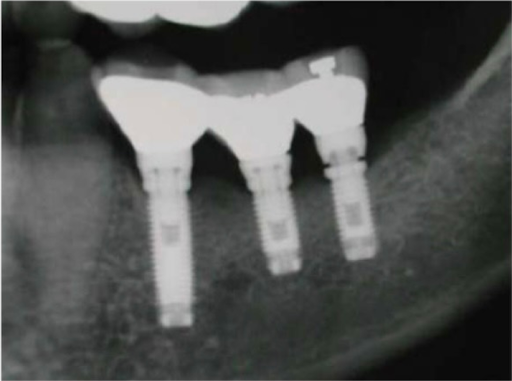

Phim x quang cầu răng sau hàm dưới trên implant Branemark, cho thấy thất bại khi gắn abutment sau cùng trên khớp hex của implant và vít cầu răng bị lỏng.

Phim xquang cầu răng 3 đơn vị trên implant Brenmark chịu lực quá tải. Bệnh nhân nghiến răng. Implant răng trước bên phải đã từng có một vít abutment gãy trước đó, phần nửa trên của phần vít được lấy ra và thay thế bằng một vít gold (thấy cản quang hơn) nhưng phần chóp không thể lấy ra được. Implant phía xa bên trái có tiền sử tương tự là gãy implant tại vị trí ngang chóp của vít abutment. Tình huống này yêu cầu tháo bỏ hay chôn vùi luôn implant gãy.